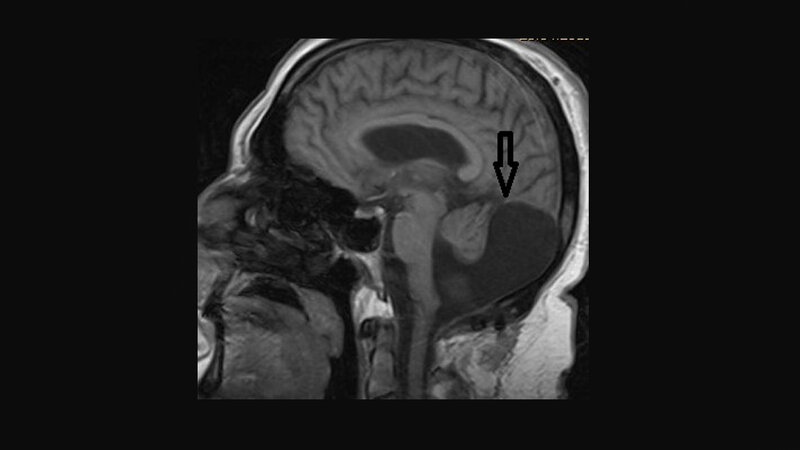

Das Dandy-Walker-Syndrom ist eine der Malformationen der hinteren Schädelgrube. Es ist durch eine Hypoplasie des Vermis cerebelli, zystische Dilatation des 4. Ventrikels und Vergrößerung der hinteren Schädelgrube charakterisiert. Eine Assoziation der Dandy-Walker-Malformation mit einer Syringomyelie ist sehr selten, möglich mit tumorösen Veränderungen.

Dandy-Walker syndrome is one of the malformations in the posterior fossa of the head. It is characterized by hypoplasia of the cerebellar vermis, cystic dilatation of the fourth ventricle and enlargement of the posterior fossa. The association between the Dandy-Walker complex and syringomyelia is very rare, possible with tumours.